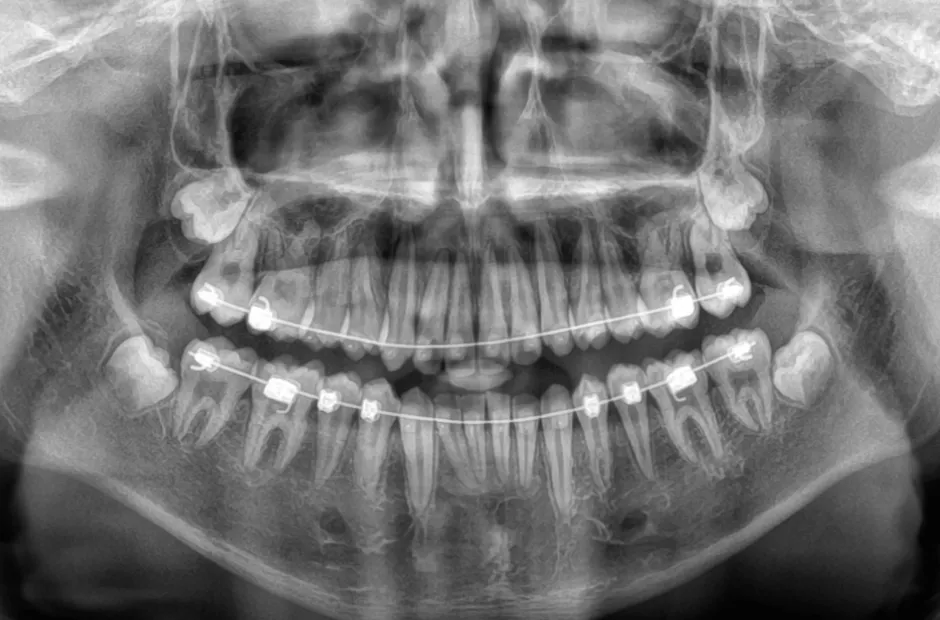

治療中

治療後